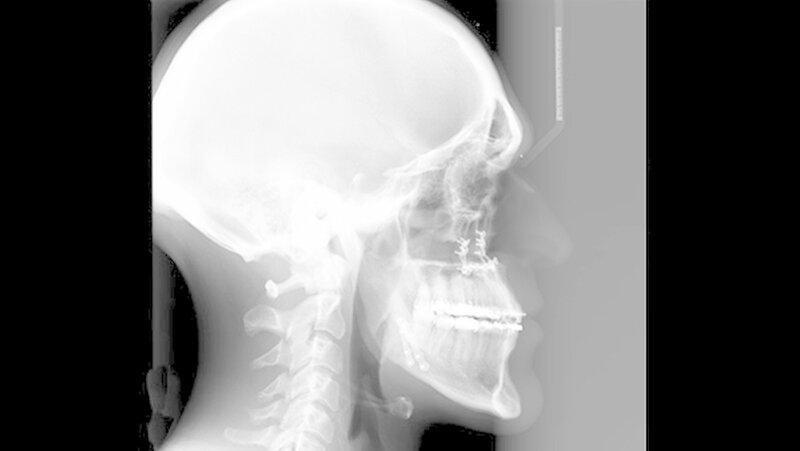

Der Fall: Progenie durch Akromegalie

Der Patient stellte sich erstmals 2010 in der Stuttgarter MKG-Spezialsprechstunde vor. Im ersten Schritt wurde der Tumor an der Hirnanhangdrüse über die Nase entfernt. In interdisziplinärer Zusammenarbeit mit einem Fachzahnarzt für Kieferorthopädie wurden im ersten Behandlungsabschnitt die Zahnbögen ausgeformt. Um den Oberkiefer in der Breite zu dehnen, führten die Stuttgarter Zahnärzte im Oktober 2012 eine chirurgisch unterstützte Gaumennahterweiterung durch.

Das deutlich harmonischeres Profil drei Monate nach der Operation: Im Mai des nachfolgenden Jahres wurden die Metallplatten in einem ambulanten Eingriff wieder entfernt. Eine Multibandapparatur hält die Zähne noch "in der Reihe". Der Patient kann heute dank der individuellen innovativen Behandlung ein normales Leben führen, die Gesichtsästhetik und seine Kaufunktion sind vollständig wiederhergestellt.

Am Gesichtsschädel führen die Wachstumshormone zu einem persistierenden Wachstum des Unterkiefers. Die Körperproportionen erscheinen dadurch extrem unharmonisch und vergröbert. Der daraus entstehende Fehlbiss ist häufig auch verantwortlich für degenerative Kiefergelenkserkrankungen.